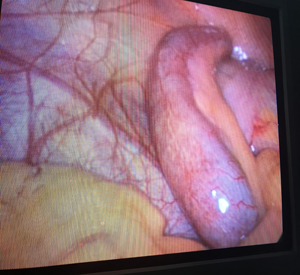

The official name of the appendix is vermiform appendix, which means "worm-like appendage". It is a small, pouch-like sac of tissue that is located in the first part of the colon (cecum) in the lower- right abdomen. Appendix plays a role in immune function by its lymphatic tissue. It usually harbors bacteria.

At Remedy Hospital we offer surgery for all conditions of appendix like appendicitis, appendicular malignancy, and mucocele of appendix. We offer surgery by latest technique (Laparoscopic Appendectomy) as well as time tasted conventional technique (Open Appendectomy).